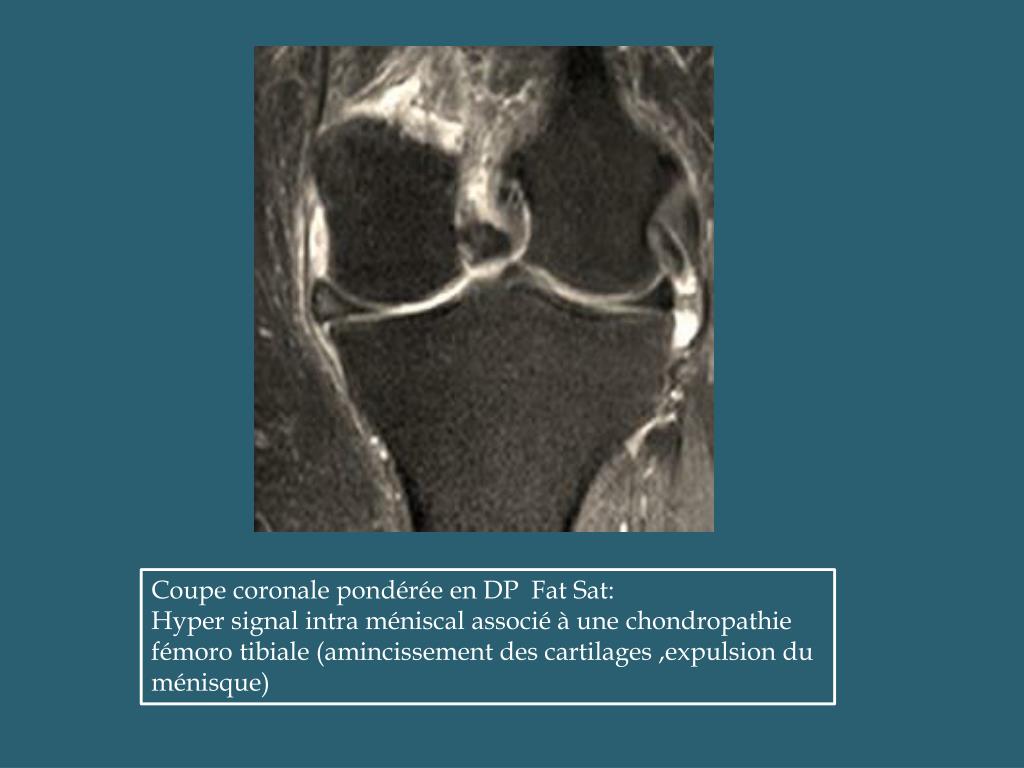

ATLAS IRM DES LESIONS MENISCO LIGAMENTAIRES DU GENOU Lesion Plaque Palmaire Irm Classification des lésions en hyperextension de l'articulation intrephalangienne: Les avulsions de la plaque palmaire de l’articulation ipp sont des lésions courantes. Rupture complète, sans avulsion osseuse, de la plaque palmaire (flèches blanches) au niveau de la quatrième interphalangienne proximale. Schéma représentant l'aspect normal et l'avulsion de la plaque palmaire: Dans les cas de rétraction irréductible de la plaque palmaire, un. Lesion Plaque Palmaire Irm.

Imagerie par résonance magnétique ou IRM de l'articulation du genou PDW Lesion Plaque Palmaire Irm Les avulsions de la plaque palmaire de l’articulation ipp sont des lésions courantes. Classification des lésions en hyperextension de l'articulation intrephalangienne: Rupture complète, sans avulsion osseuse, de la plaque palmaire (flèches blanches) au niveau de la quatrième interphalangienne proximale. L’irm est une méthode performante pour évaluer les lésions aiguës et chroniques de la plaque palmaire et des ligaments collatéraux des.. Lesion Plaque Palmaire Irm.

PPT ATLAS IRM DES LESIONS MENISCO LIGAMENTAIRES DU GENOU PowerPoint Lesion Plaque Palmaire Irm Habituellement, un traitement conservateur à. Rupture complète, sans avulsion osseuse, de la plaque palmaire (flèches blanches) au niveau de la quatrième interphalangienne proximale. L’irm est une méthode performante pour évaluer les lésions aiguës et chroniques de la plaque palmaire et des ligaments collatéraux des. Avulsion simple de la plaque palmaire. Elles se produisent le plus souvent sur un mécanisme en. Lesion Plaque Palmaire Irm.